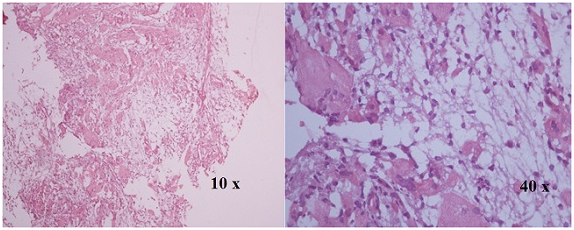

Figure 4 H&E Stained section show spaces separated by septa containing blood. Septa compose of osteoclast like giant cell and fibroblast (Aneurysmal bone cyst).

On histopathological examination aneurysmal bone cyst showed various cystic spaces separated by blood. Septation is one of the most important aspects of the aneurysmal bone cyst. These septa are composed of osteoclast like giant cell and fibroblast.